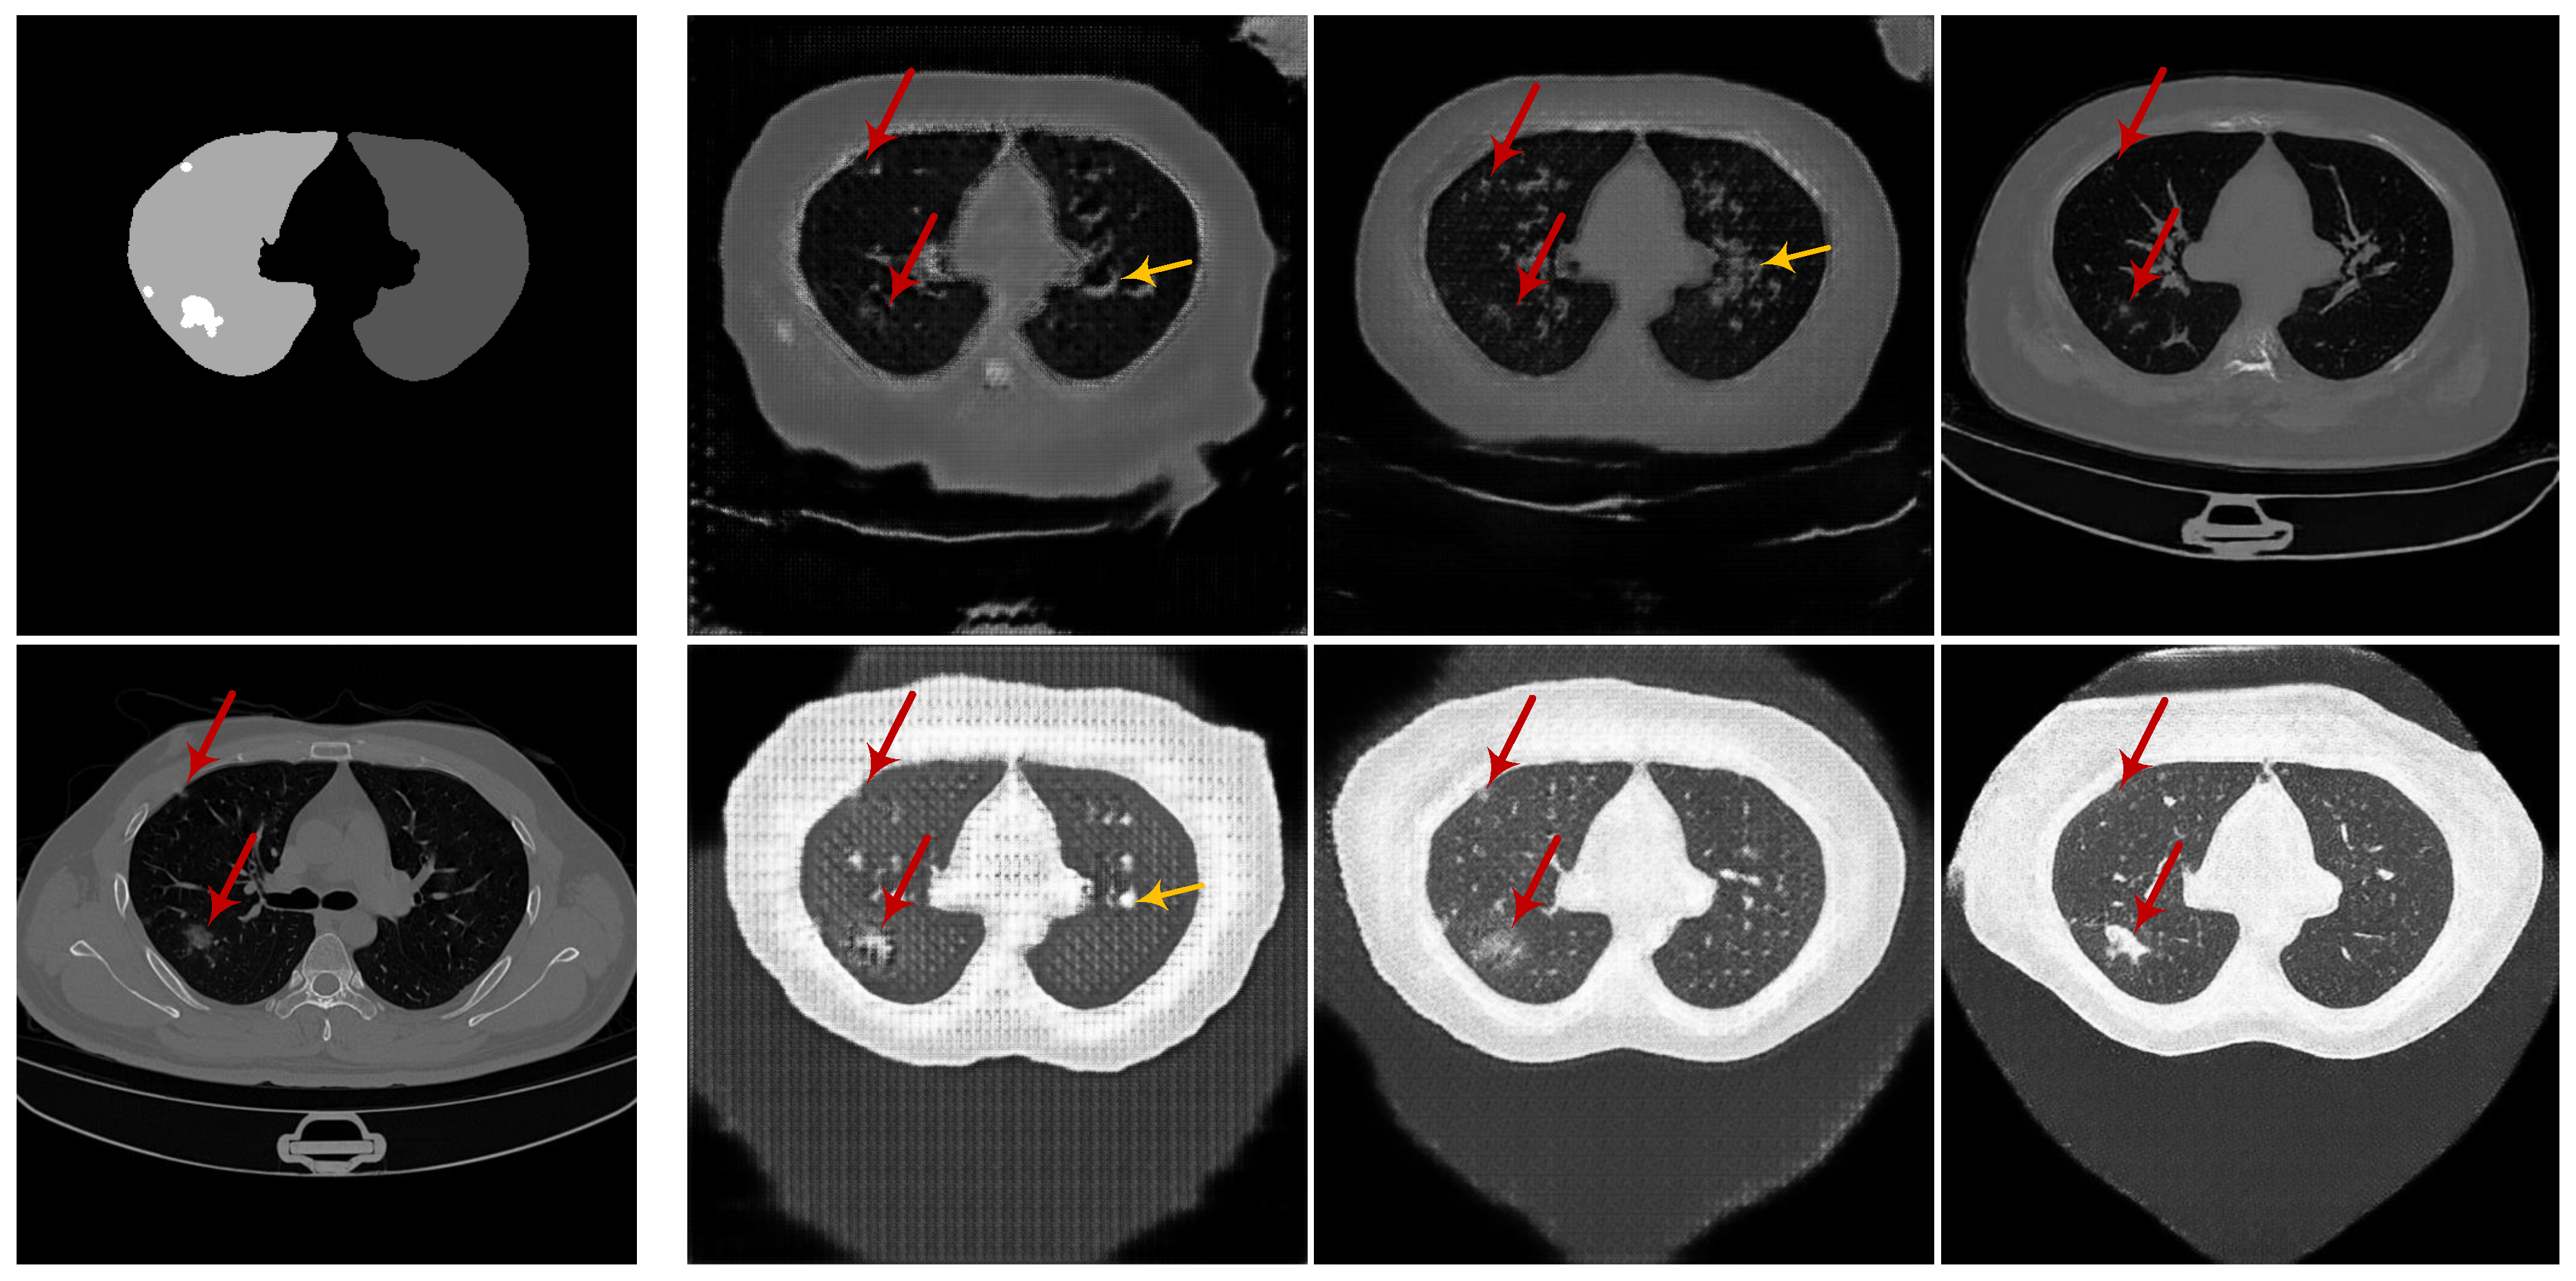

3.1. Experiments on Synthesizing Radiological Images

3.1.4. Evaluation on the Ability of CoSinGAN in Generating Diverse Samples